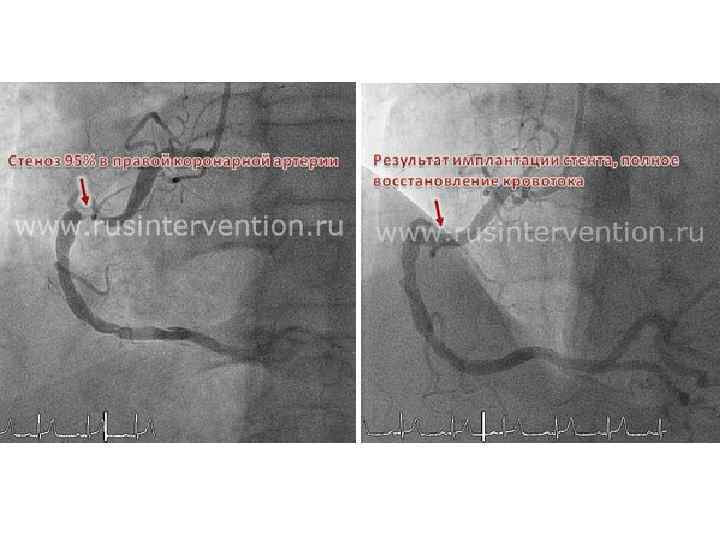

Операция рентгендік бақылаумен өтеді • Диагностика сатысында коронароангиография жүргізіледі, тарылу көлемін, орынын анықтау үшін • Доступ – сан артериясы • Арнайы катетер арқылы контрастты зат енгізіледі де, рентен түсіріледі • Катетер арқылы өткізгішті жібереді, ал өткізгіште баллонды стент орналасады

Операция рентгендік бақылаумен өтеді • Диагностика сатысында коронароангиография жүргізіледі, тарылу көлемін, орынын анықтау үшін • Доступ – сан артериясы • Арнайы катетер арқылы контрастты зат енгізіледі де, рентен түсіріледі • Катетер арқылы өткізгішті жібереді, ал өткізгіште баллонды стент орналасады

Стент тамырішілік протез. Зақымдалған тамырдың диаметрін сақтап тұру үшін қажет. • Дәрілік қабаты бар стент. • Металл – кобальт/хром • Дәрілері цитостатиктер Rapamycin (Sirolimus) и Paclitaxel (Taxol)

Стент тамырішілік протез. Зақымдалған тамырдың диаметрін сақтап тұру үшін қажет. • Дәрілік қабаты бар стент. • Металл – кобальт/хром • Дәрілері цитостатиктер Rapamycin (Sirolimus) и Paclitaxel (Taxol)

Көрсеткіштері: Жедел МИ 3 -4 ФК стенокардия Симптомсыз жүретін миокард ишемиясы Опреациядан кейінгі қайталама МИ Стенттан кейін жедел тромбоз Асқынулар: Жергілікті Пункция жерінде қан кету Пункция жерінде гематома Артериямен б-қан қуыстың пайда болуы Пульсирующая гематома Артерия мен вена арасында жол п. б. Қарсы көрсеткіштері: Тәж артериялардың диффузды зақымдалуы Ауыр тыныс жетіспеушілігі Ауыр бүйрек жетіспеушіліг Қан ұю патолгиясы Йод препараттрына аллергия Асқынулар: Жалпы • Контрастты затқа аллергия • Бүйрек қызметінің бұзылуы • Артерия қабырғасының зақымдалуы • МИ-сы, инсульт • Аритмия, ӨЛІМ

Көрсеткіштері: Жедел МИ 3 -4 ФК стенокардия Симптомсыз жүретін миокард ишемиясы Опреациядан кейінгі қайталама МИ Стенттан кейін жедел тромбоз Асқынулар: Жергілікті Пункция жерінде қан кету Пункция жерінде гематома Артериямен б-қан қуыстың пайда болуы Пульсирующая гематома Артерия мен вена арасында жол п. б. Қарсы көрсеткіштері: Тәж артериялардың диффузды зақымдалуы Ауыр тыныс жетіспеушілігі Ауыр бүйрек жетіспеушіліг Қан ұю патолгиясы Йод препараттрына аллергия Асқынулар: Жалпы • Контрастты затқа аллергия • Бүйрек қызметінің бұзылуы • Артерия қабырғасының зақымдалуы • МИ-сы, инсульт • Аритмия, ӨЛІМ